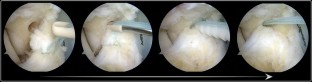

Thirteen patients [12 men and 1 woman, median age 32 (15–54) years] with rotational ankle instability were treated by arthroscopic means after failing non-operative management. Median follow-up was 35 (18–42) months. Using a suture passer and knotless anchors, the ligaments were repaired with an arthroscopic all-inside technique.

Fig. 4